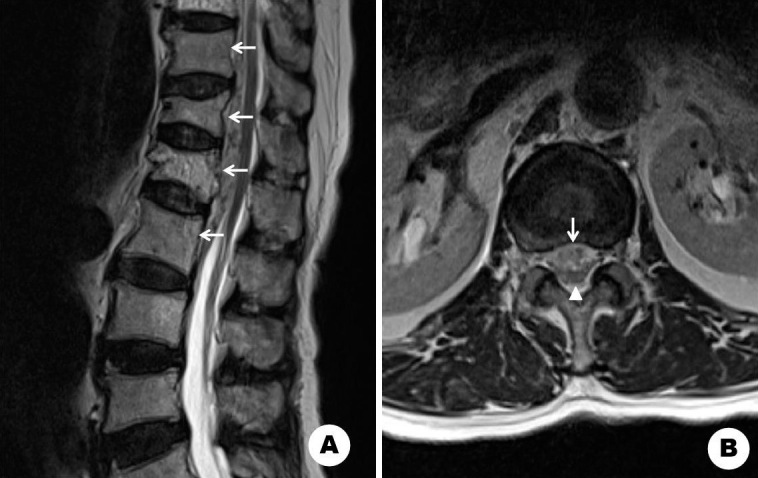

Complete Resolution of Hematoma after Vertebroplasty in Epidural Hematoma Associated with Acute Osteoporotic Vertebral Fracture: A Case Report.

急性骨质疏松性椎体骨折伴硬膜外血肿椎体成形术后血肿完全消退1例报告。